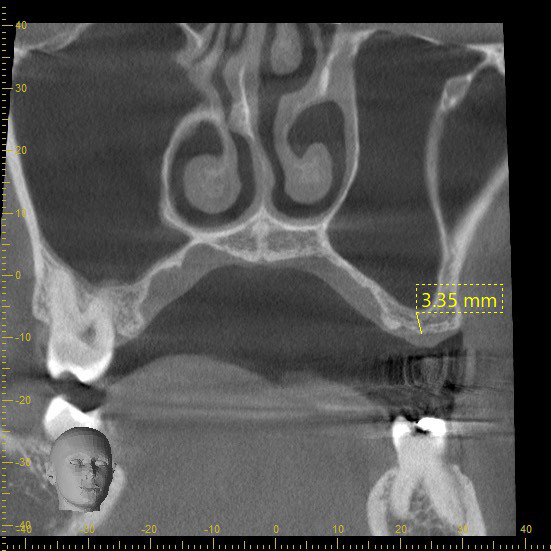

歯が割れたり親知らずなど、やむをえず歯を抜いた後、心配なのは出血や抜歯後の痛みだと思います。

当院では、抜歯後にテルプラグという抜歯創用保護材を填入することをお勧めしています。

テルプラグを抜歯窩に填入することにより、傷口の保護、肉芽形成を促し、痛みを和らげる効果が期待されます。